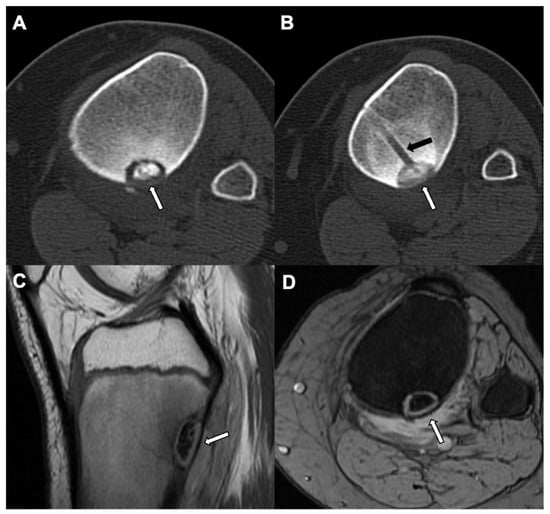

5. Osteoid Osteoma

| Radiographic/CT features | Juxtacortical, well-circumscribed homogenous sclerotic lesion | Homogenous intra-medullary sclerotic focus with spiculated margins | Small (less than 2 cm) cortical lucency with extensive surrounding sclerosis | Expansile large (more than 2 cm) lucent lesion with matrix mineralization |